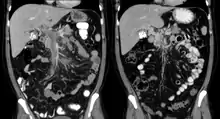

Portal vein thrombosis on computed tomography (left) and cavernous transformation of the portal vein after 1 year (right)

The diagnosis of portal vein thrombosis is usually made with imaging confirming a clot in the portal vein; ultrasound is the least invasive method and the addition of Doppler technique shows a filling defect in blood flow. PVT may be classified as either occlusive or nonocclusive based on evidence of blood flow around the clot.[5] An alternative characterization based on site can be made: Type 1 is limited to the main portal vein, Type 2 involves only a portal vein branch (2a, or 2b if both branches are affected), and Type 3 if clot is found throughout both areas.[8] Determination of condition severity may be derived via computed tomography (CT) with contrast, magnetic resonance imaging (MRI), or MR angiography (MRA). Those with chronic PVT may undergo upper endoscopy (esophagogastroduodenoscopy, EGD) to evaluate the presence of concurrent dilated veins (varices) in the stomach or esophagus.[3] Other than perhaps slightly elevated transaminases, laboratory tests to evaluate liver function are typically normal.[1] D-dimer levels in the blood may be elevated as a result of fibrin breakdown.